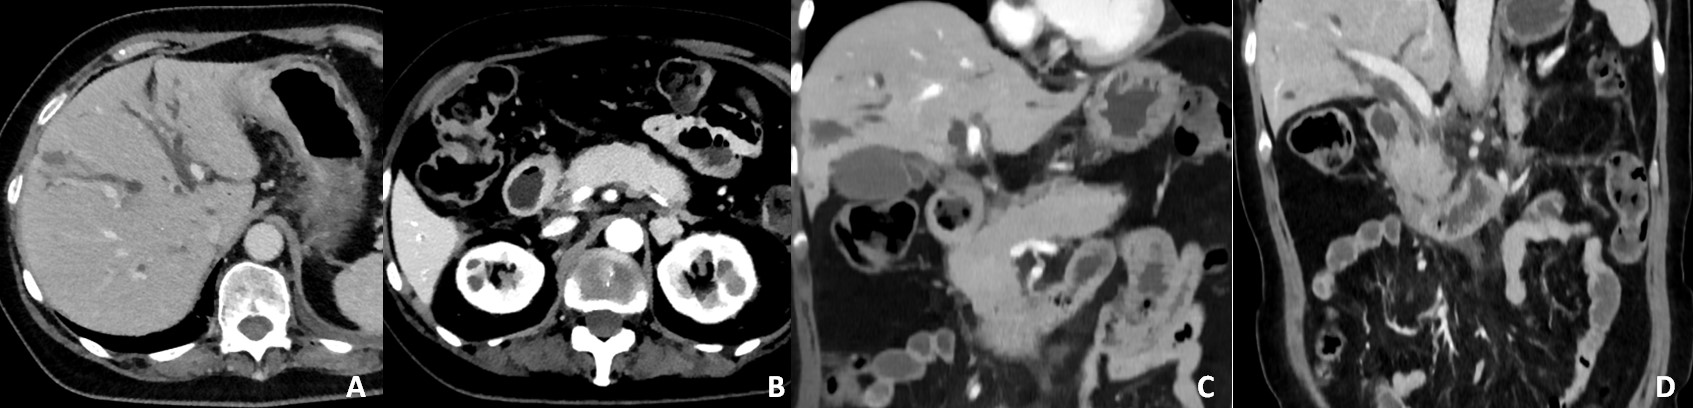

The CT scan revealed diffuse dilatation of intra-hepatic biliary ducts (Figure 1A). Diffuse enlargement of the pancreas and peri-pancreatic fat stranding were also noted, suggesting inflammatory pattern (Figure 1B-C). Alongside dilatation of intra-hepatic bile ducts, the MRI scan showed a long stricture of the common bile duct (Figure 2A, 2C). Increased wall thickness of the common bile duct was also observed (Figure 2A).

Diffuse restricted diffusion of the pancreatic parenchyma (Figure 2E-F) was identified and slight loss of lobulation (Figure 2D), indicating possible autoimmune pancreatitis.

Restricted diffusion of the intrahepatic bile ducts wall (Figure 2B) and increased wall thickness of the gallbladder (Figure 2A) was also noted, suggesting concomitant cholangitis.

Figure 2: Cholangiopancreatography MRI (A) coronal T2W (C) radial CPRM; (D) axial T2W (B, E) DWI (F) ADC map; showing increased thickness of the pancreatic parenchyma (A, B) and diffuse restricted diffusion of the parenchyma (E, F). Diffuse intra-hepatic bile duct dilatation and dilatation of the distal part of the extra-hepatic bile duct, with increased thickness of the bile duct wall (A, C). A long regular stenosis of the distal part of the extra-hepatic bile duct is also present (C). Restricted diffusion of the intra-hepatic bile ducts is shown (B).

In the present case, diffuse pancreatic enlargement was observed with peri-pancreatic fat stranding (Figure 1B-D; Figure 2D), along with restricted diffusion, suggesting inflammatory pattern. Additionally, diffuse intrahepatic and focal extrahepatic bile duct dilatation were observed (Figure 2C), with diffuse thickening of the extrahepatic bile duct wall and of the gallbladder wall (Figure 2A). These findings suggest concomitant ICI-induced cholangitis.